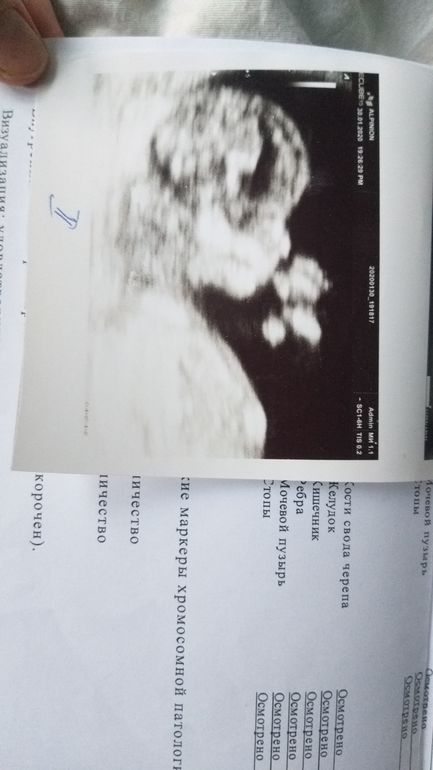

11 нед. 6 дней

Первый скрининг

Дочин профиль

Вот сыночкин профиль, лапу сосет